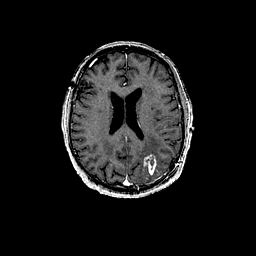

Glioma overlay -- Slice #72